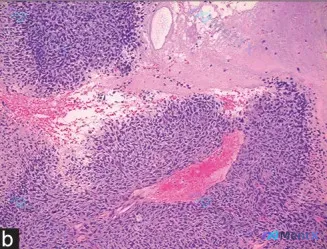

网上看到一份病理HE切片的描述和分析,有点意思,抛出来大家聊聊读片思路: > 显微镜下见: > 1. 细胞密集呈实性巢状/片状,圆形/卵圆形/梭形,核浆比显著增高,核大小基本一致(单调性),染色质深染,核仁不明显; > 2. 间质稀少,但血管极丰富,可见扩张充血的血管穿插于细胞团间,伴区域性出血;...

今天整理了一个挺有警示意义的免疫组化读片病例,差点走了弯路,和大家一起梳理下思路。 先看提供的核心信息 - 影像描述:vWF(von Willebrand factor)免疫标记,毛细血管内皮细胞胞质阳性,间质细胞阴性(红色圆圈标注区域);20μm 比例尺,40x 放大。 - 最初的读片偏差:曾把棕...